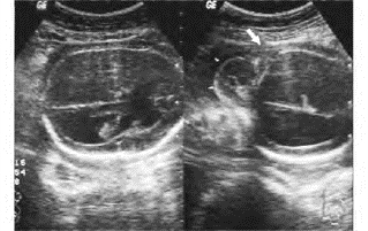

1.38.12十二、胎儿畸形